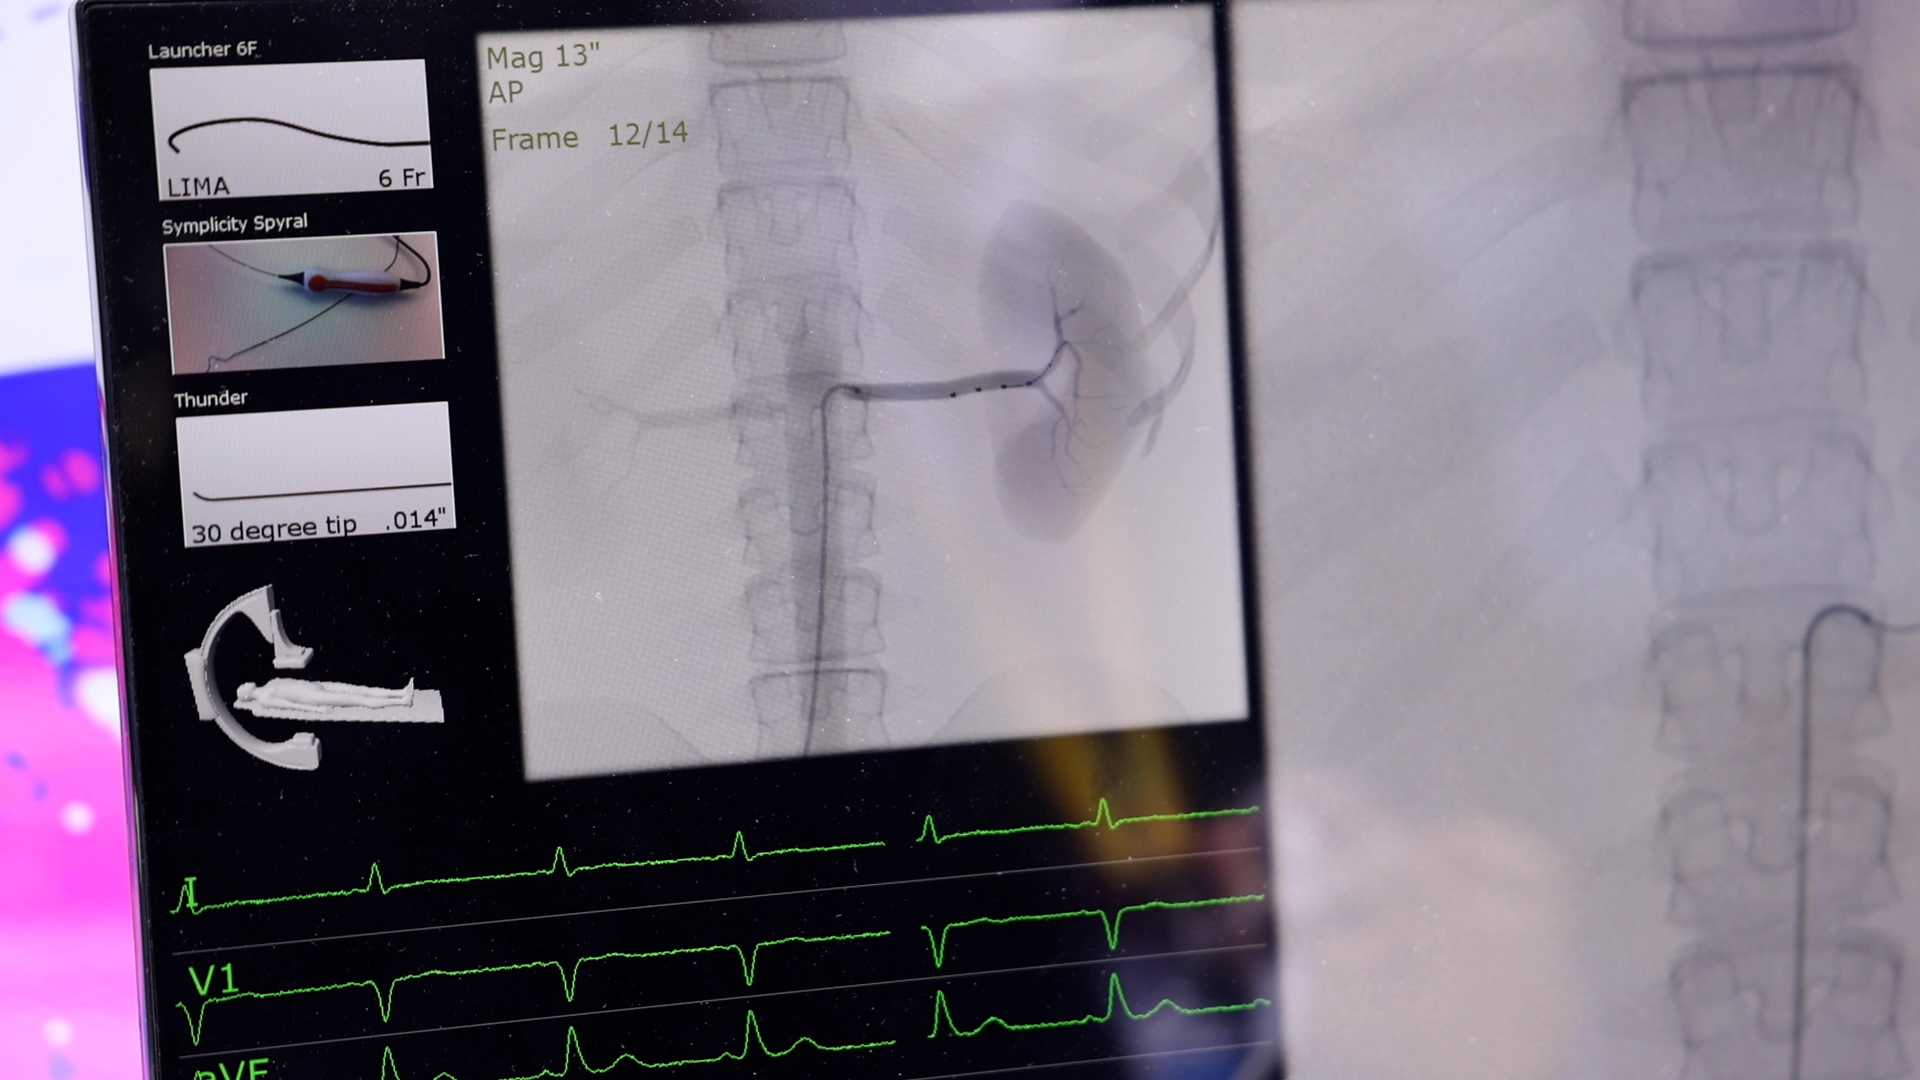

据《中国心血管健康与疾病报告2021》显示,我国高血压患者总量达到2.45亿。高血压作为慢性疾病,是名副其实的“隐形杀手”。11月6日,进博会医疗保健展区美敦力展台,心血管健康联盟和美敦力携手发起高血压介入诊疗规范化项目,美敦力创新的RDN疗法产品Symplicity Spyral肾动脉交感神经多极射频消融导管亮相进博会。目前设备已特许落地博鳌乐城先行区,预计于23年在国内正式上市。

RDN疗法运用微创介入方式,通过特定器械,阻断引发血压升高的交感神经,使过度兴奋的神经冷静下来,从而实现一次手术,长期降压的效果。目前已被多个国家和地区的临床专家认可为除生活方式干预和药物治疗之外,高血压治疗的第三种选择。RDN手术创伤小、手术时间短、术后恢复快,是血压控制不佳患者的新选择。患者可以在术后不增加药物,甚至部分患者在术后实现减少或停药,亦可较好的控制血压,帮助提升患者生活质量。希望这项新型高血压介入治疗方式能为更多中国患者带来获益。